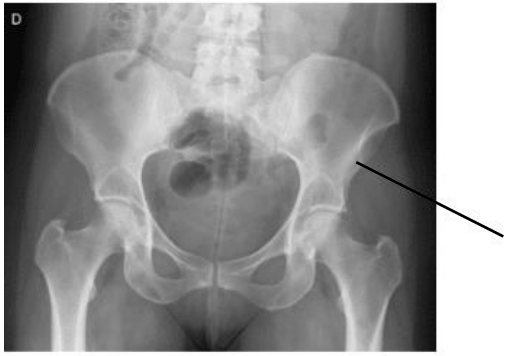

No exame abaixo podemos visualizar um detalhe anatômico ósseo denominado: